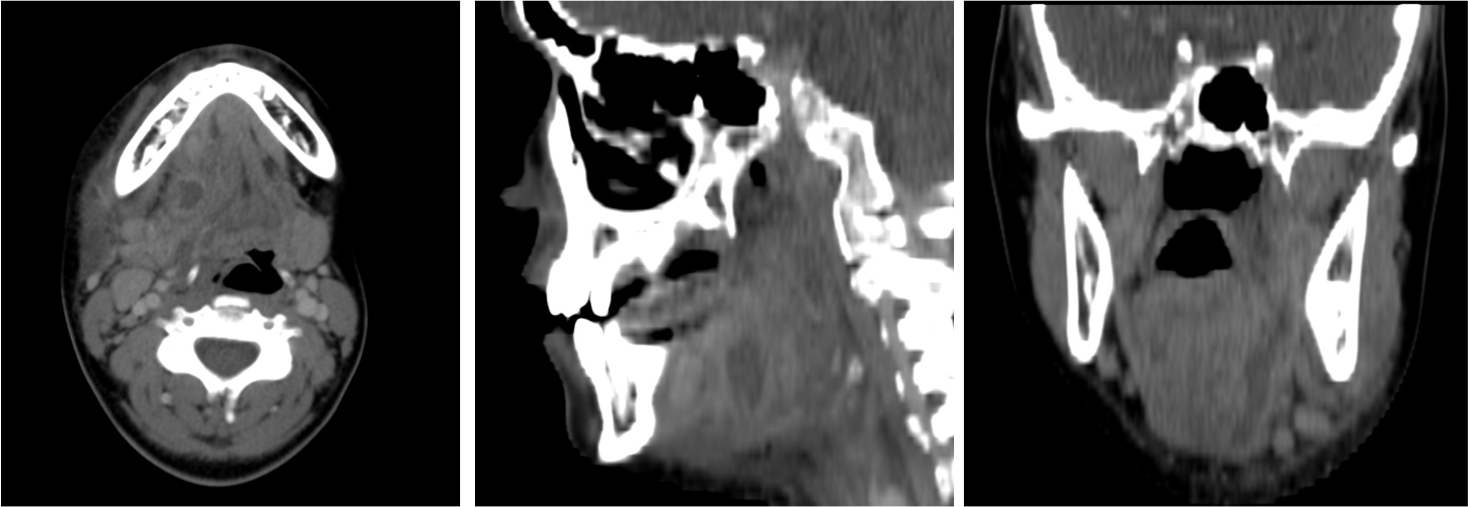

ENFERMEDAD DENTAL.

Ante pacientes con hinchazon facial, se debe sospechar enfermedad endodontal.

Puede ser identificada mediante TC por el estudio de las racies dentales, las cuales presentarán una lucencia o baja densidad que las rodea = signo de las raíces flotantes = afectación endodental = caries bacteriana que pogresa, afecta la pulpa y finalmente dañan la raíz del diente y el hueso de alrededor produciendo una osteomielitis localizada y abscesos subperiósticos o colecciones que se desplazan a tejidos superficiales.